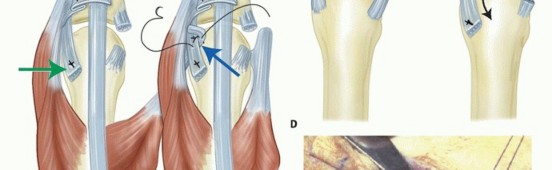

This is the most critical biomechanical step of the procedure. The EDC tendon must be relocated from the ulnar gutter and secured over the exact dorsal apex of the metacarpal head. To achieve this, the ulnar sagittal band—which is tethering the tendon ulnarly—must be completely divided.

Once the ulnar release is complete, the EDC tendon is manually centralized. The attenuated radial sagittal band is then reefed (imbricated) and sutured over the centralized tendon to hold it in place. We utilize non-absorbable, braided sutures (e.g., 4-0 Ethibond or Ticron) in a horizontal mattress